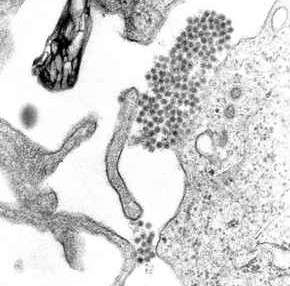

Once inside the skin, dengue virus binds to Langerhans cells (a population of dendritic cells in the skin that identifies pathogens).[39] The virus enters the cells through binding between viral proteins and membrane proteins on the Langerhans cell, specifically the C-type lectins called DC-SIGN, mannose receptor and CLEC5A.[24] DC-SIGN, a non-specific receptor for foreign material on dendritic cells, seems to be the main point of entry.[27] The dendritic cell moves to the nearest lymph node. Meanwhile, the virus genome is translated in membrane-bound vesicles on the cell's endoplasmic reticulum, where the cell's protein synthesis apparatus produces new viral proteins that replicate the viral RNA and begin to form viral particles. Immature virus particles are transported to the Golgi apparatus, the part of the cell where some of the proteins receive necessary sugar chains (glycoproteins). The now mature new viruses are released by exocytosis. They are then able to enter other white blood cells, such as monocytes and macrophages.[24]